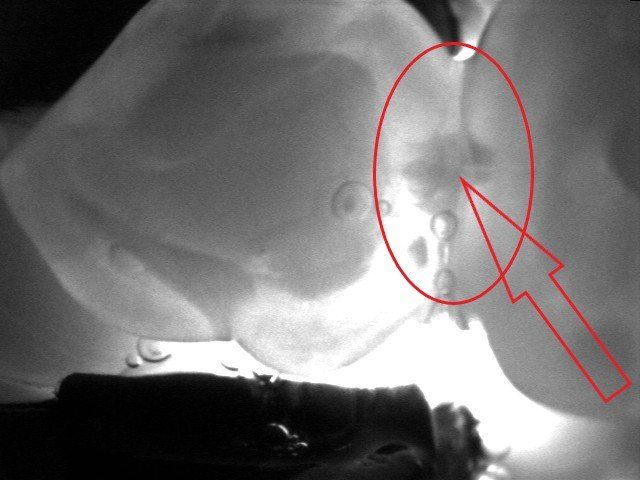

Viene presentato un caso in cui si evidenzia la presenza di carie mesiale e distale su un 25 (secondo premolare superiore di destra) attraverso l'analisi radiografica. Si deve sottolineare la difficoltà di metterne in risalto e di determinarne l'estensione solo mediante la radiografia. Nella fotografia successiva, l'entità e l'estensione della carie appaiono notevolmente superiori a quanto potesse essere dedotto dalla sola radiografia. Si mostra poi la cavità ripulita dalla carie, evidenziando la perdita di tessuto dentale causata da essa. Infine, si presenta l'otturazione appena completata, con i segni della cartina da articolazione ancora visibili, utilizzata per verificare l'altezza della cura, che richiederà successivamente un ulteriore rifinitura e lucidatura.

Un particolare utilizzo di due fasci laser e di un sensore che trasforma la transilluminazione in immagine visibile sul monitor del computer trova un utilizzo anche nella diagnosi della carie qualora l’immagine radiografica risulti dubbia o non dirimente di lesione cariosa. Ecco un esempio in cui radiologicamente si vede un’immagine non chiaramente rapportabile ad una carie come indicato dalle frecce nella radiografia a fianco. Con l’ausilio del laser si riesce ad evidenziarne completamente i limiti e la grandezza come visibile dalle due immagini e dalle frecce che indicano la carie. Tuttavia, per correttezza, va spiegato che l’efficacia di questa indagine può essere effettuata solo in determinate circostanze cliniche e che le radiografie risultano sempre necessarie.